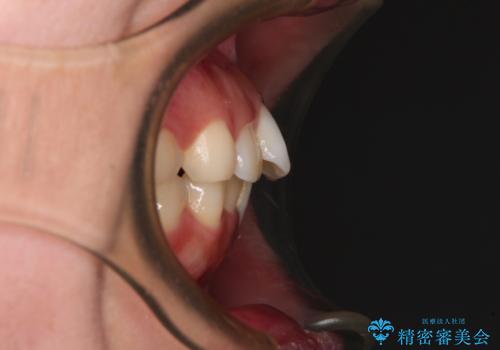

- 全体的なデコボコと口元の突出感を改善したいとのことで来院された患者様です。

このままデコボコを整えるとさらに突出感が増すため、上下左右の第一小臼歯を抜歯し、ワイヤー装置にて矯正しました。